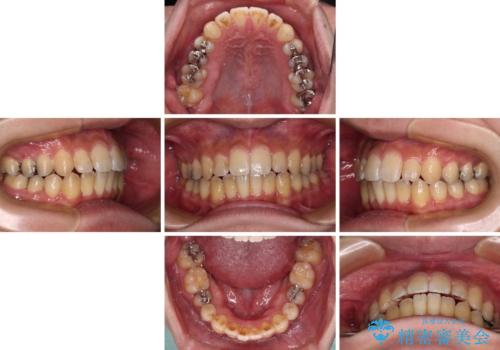

オープンバイトと目立つ銀歯 インビザライン矯正とセラミック修復治療

開咬の治療は、前歯を閉じるように動かすとともに、上下臼歯を圧下(骨内にめり込ませる)させることで進めて行きます。

インビザラインは臼歯の圧下を効果的に行えるため、インビザラインを用いて矯正治療を行うこととしました。

銀歯については、矯正治療により咬合関係を改善し、矯正治療後半に修復治療を行うこととしました。

修復治療後に細かい部分をインビザラインで再度仕上げるプランとしました。